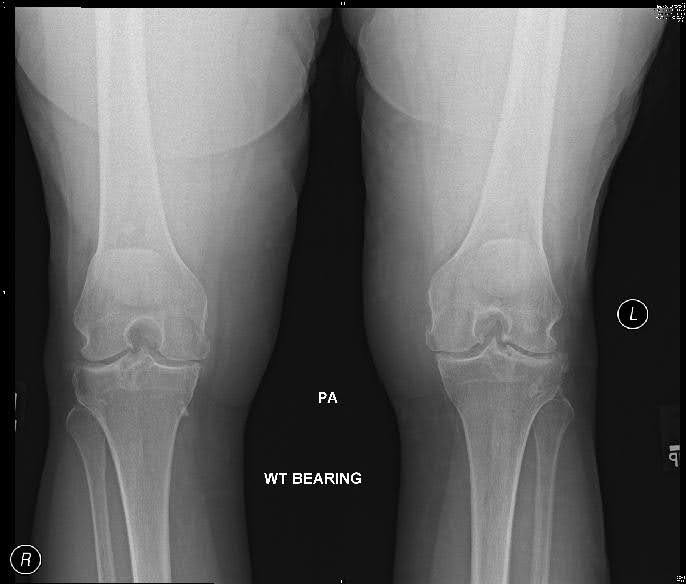

Se trata de una mujer de 66 años con dolor bilateral de rodilla, empeorado a la izquierda. Ha probado un tratamiento conservador durante varios años, que incluye la modificación de la actividad y los analgésicos orales, sin ningún efecto significativo. Los antecedentes quirúrgicos significativos incluyen dos procedimientos artroscópicos en rodillas bilaterales en los últimos siete años.

Las vistas AP que soportan peso, incluidas las rodillas bilaterales, las vistas laterales y del amanecer, son necesarias para evaluar radiográficamente la osteoartritis de rodilla. Los hallazgos críticos de la osteoartritis de rodilla en el examen radiológico son los siguientes:2

- Estrechamiento del espacio articular

- Osteofitos

- Esclerosis subcondral

- Quistes subcondrales

- Pérdida de stock óseo

- Malalignment

- Deformidad en varo o valgo

Encontrar osteofitos en las radiografías es lo que mejor diferencia la osteoartritis de la artritis reumatoide y otras artritis. Un criterio sensible y específico para la artrosis de rodilla es la combinación de dolor de rodilla, aspecto radiológico de los osteofitos y uno o más de los siguientes: edad mayor de 50 años, rigidez matutina inferior a 30 minutos o crepitación en movimiento activo.

Se deben utilizar las vistas bilaterales de soporte de peso para comparar el lado afectado con el no afectado. La artrosis debe evaluarse en cada uno de los tres compartimentos de la rodilla: medial, lateral y patelofemoral. Hay que tener en cuenta que hasta el 30% de los adultos mayores de 65 años presentarán un aspecto radiográfico de la artrosis, pero un tercio de estos individuos serán asintomáticos. 3 Por lo tanto, es importante correlacionar los hallazgos clínicos y radiográficos para llegar a un diagnóstico de osteoartritis de rodilla sintomática, una entidad clínicamente relevante.

Figura 1. Radiografías preoperatorias.